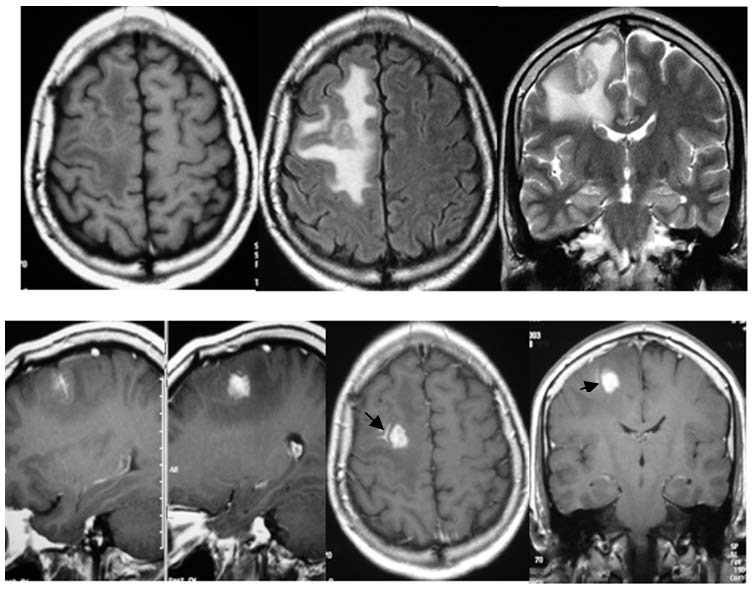

Acompañamos la presente comunicación con imágenes de RM en las que se grafica el «vaso centinela» a nivel frontal derecho (figura 1), fronto-parietal derecho (figura 2) y fronto-temporal derecho (figura 3).

Imágenes de RM sin gadolinio en corte axial en T1 y Flair, y en corte coronal en T2. RM con gadolinio: cortes sagital, axial y coronal. Se observa un granuloma frontal derecho, cortico-subcortical, con gran edema perilesional y masa captadora. La flecha señala un «vaso centinela» captador.